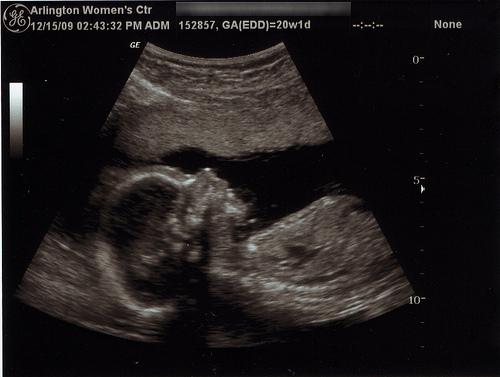

El parto prematuro es sumamente frecuente, se lo considera espontáneo cuando ocurre antes de que el feto cumpla las 37 semanas de gestación y se trata de un desenlace que puede estar vinculado a diversos motivos como por ejemplo que la mujer atraviese una infección, que se trate de una madre adolescente, que sea un caso de embarazo múltiple, que sufra algún traumatismo o pase por una situación de fuerte estrés.

La Organización Mundial de la Salud emite cifras que indican que más de 15 millones de bebés nacen de manera prematura al año en todo el mundo, siendo números que se encuentran en aumento permanente, teniendo grandes riesgos aquellas mujeres que se embarazan con edad elevada o que practican tratamientos de fertilidad, entre muchos factores igualmente influyentes.